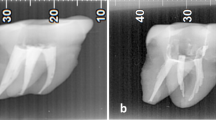

A total of 327 post-retained crowns were examined radiographically and a number of features were assessed including the length of post, length of remaining root filling, periapical condition, fit and angulation of the post and quality of root filling. The post length was equal to or greater than that of the crown in only 34% of cases. Although the majority of posts fitted well laterally, 43% did not extend longitudinally as far as the end of the prepared post hole. Some 20% deviated from the line of the root canal but the number of actual lateral perforations was small. A total of 47% of the teeth had areas of radiolucency around the root apices. A majority of root fillings were judged to be unsatisfactory and there was no radiographic evidence of any root filling at all in nearly 10% of cases